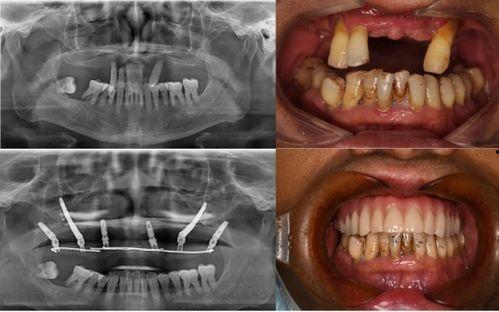

首先,让我们来回顾一下这个事件。据网友爆料,佛山某口腔医院在进行种植牙手术时,竟然出现了严重的医疗事故。视频中,一位患者在手术过程中突然大出血,医护人员却显得手忙脚乱,场面一度十分混乱。这个视频一经曝光,立刻引起了广大网友的关注和热议。